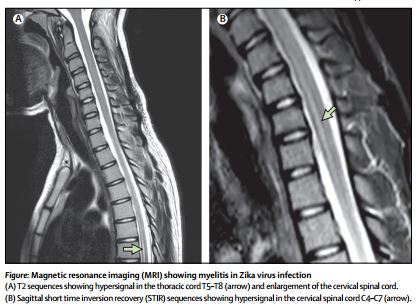

Một báo cáo trường hợp (case report) công bố trực tuyến trên Tạp chí The Lancet mô tả một cô gái có Zika virus dương tính 15 tuổi ở Guadeloupe đã phát triển viêm tủy cấp tính (viêm tủy sống) gây ra đau lưng, tê liệt và rối loạn chức năng bàng quang chứng tỏ virus Zika ảnh hưởng chủ yếu đến hệ thần kinh.